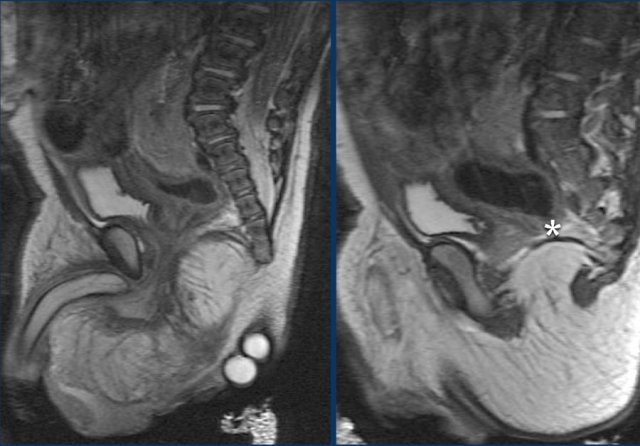

Initially plain films and ultrasound can be used to show the position of the malformation and the need for a colostomy.

At a later stage and prior to definitive surgery a combination of fluoroscopic studies and MRI will be used to show the complex anatomy of anorectal, genitourinary, pelvic and perineal structures and associated fistulas.

Anal atresia is part of the VACTERL malformations and patients should be screened for concomittant anomalies.